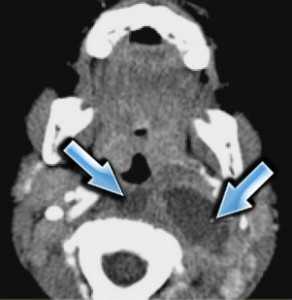

(Слева) МРТ Т1ВИ FS c КУ, аксиальная проекция. В правом сонном пространстве визуализируется крупное новообразование, однородно накапливающее контрастное вещество. Такой облик опухоли весьма характерен для шванномы. Шванномы данной локализации могут происходить из ЧН IX-XII. Чаще всего встречаются шванномы блуждающего нерва.

(Справа) КТ в костном окне, аксиальная проекция. Фестончатые изменения костных структур в области ската характерны для шванном. Шваннома, локализующаяся в носоглоточном отделе сонного пространства, может ремоделировать костную ткань основания черепа. Для параганглиом, напротив, характерен деструктивный рост.